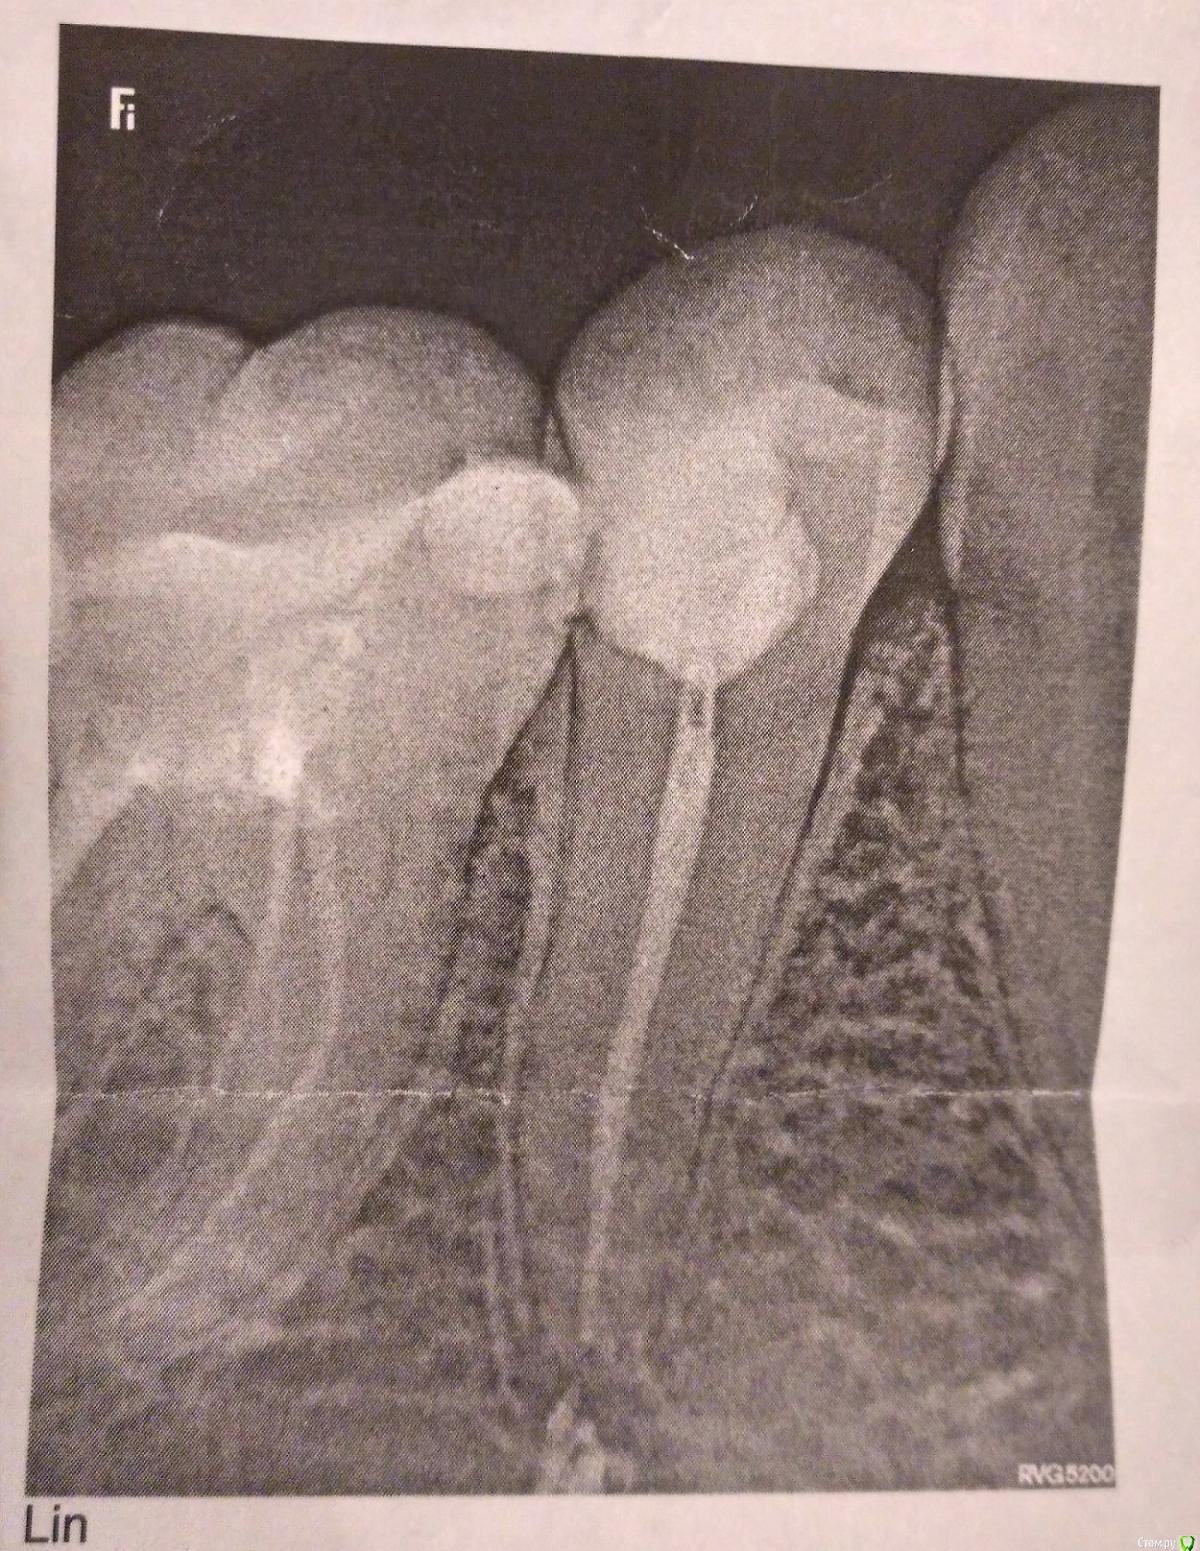

ksia Опубликовано 24 ноября, 2017 Поделиться Опубликовано 24 ноября, 2017 Здравствуйте! 17 октября обратилась с жалобой на ноющие боли неясной локализации в области 45-46 зубов. Они меня беспокоили несколько недель, но зубы не реагировали на горячее/холодное, резкой боли не было.Так как 46 был давно залечен, врачом было принято решение удалить нерв в 45 зубе. После пломбирования некоторое время зуб меня не беспокоил. Ничего не ныло, не болело примерно две недели. Потом началась та самая ноющая боль, только еще сильнее. При надкусывании на зуб боли нет, могу пережевывать пищу на этой стороне, но есть боль при постукивании по зубу. Именно по 45-ому. Был сделан снимок (прикладываю его, извините за качество), обнаружен вывод материала за верхушку. Врач направляла на физпроцедуры (квч, биоптрон, было что-то еще, увы, не помню, как называется). Бесполезно. Постоянные ощущения: ноющая боль, тяжесть в зубе, иногда будто пульсирующая боль в области этого зуба, как-будто укололи иголкой внутри. Еще есть ощущение какого-то сдавливания, напряжения. К вечеру, кажется, становится хуже, чем днем. Чтобы снизить на него нагрузку, вообще не ем на этой стороне. Ситуация продолжается уже почти 1,5 месяца и не видно этому конца. Врач говорит, что не может сказать, сколько это еще может продолжаться: "У всех по-разному, материал рассосется". Проконсультировалась с хирургом неделю назад. Сделали КТ. Его вердикт: материала выведено достаточно много, но он (материал) находится далеко от нижнечелюстного канала. Как он объяснил, ни на что эта выведенная паста не давит. Резекцию верхушки на 45 зубе делать опасно. Итог: наблюдать. Скажите, пожалуйста, действительно ли нужно ждать? Сколько это может продолжаться? Нужно ли обращаться к другому врачу и перелечивать канал? Врач, который проводил лечение, опытный, но оснащение клиники оставляло желать лучшего: даже рентгена мне не делали ни до лечения, ни после. Наверное, нужно было уйти еще на этом этапе, но врач расположила к себе, плюс в вечернее, "послеработное" время у нас не так много клиник работает. Нахожусь в подавленном состоянии, потому что эта боль в постоянном, фоновом режиме. Спасибо! PS Снимок на фото сделан 17 ноября, через месяц после лечения. Ссылка на комментарий

Marika Опубликовано 28 ноября, 2017 Поделиться Опубликовано 28 ноября, 2017 (изменено) Здравствуйте! Необходимо открыть и перелечить заново 5й зуб,излишек там останется,но боль должна будет пройти. Лучше в других условиях, чтобы на всех этапах был контроль лечения. Если будет необходимо, в дальнейшем ревизия 6 зуба. Резекцию не выход из ситуации,если проблема останется в корневом канале. Изменено 28 ноября, 2017 пользователем Marika Ссылка на комментарий

Marika Опубликовано 3 декабря, 2017 Поделиться Опубликовано 3 декабря, 2017 Не очень хорошо обтурированы каналы, необходим другой снимок. Вы решили проблему или боль прошла самостоятельно?! Ссылка на комментарий